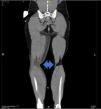

This is the case of a man with soft tissue septic shock due to Streptococcus pyogenes after trauma. Hematogenous spread with necrotizing fasciitis in the extremities (surgical resection) and meningitis with brain abscess (craniectomy and evacuation). Computed tomography (CT) with contrast: edema in the subcutaneous tissue of the left arm and muscle bellies, and a collection on the medial side of the right leg (Fig. 1, blue arrow). Right parietooccipital lobar cranial hematoma, vasogenic edema, and traumatic subarachnoid hemorrhage in the cisterns, with an increased mass effect (blurring of sulci and compression of the right lateral ventricle) (Fig. 2, orange box). Cranial MRI after clinical deterioration (Fig. 3): right occipitotemporal collection of 3.5 cm × 9 cm, irregular hypercaptating margins, and restriction (red stars) suggestive of brain abscess, with intraventricular pus, subfalcine herniation, right uncal herniation (red arrows), and subdural hematoma at the craniectomy site (red triangle).